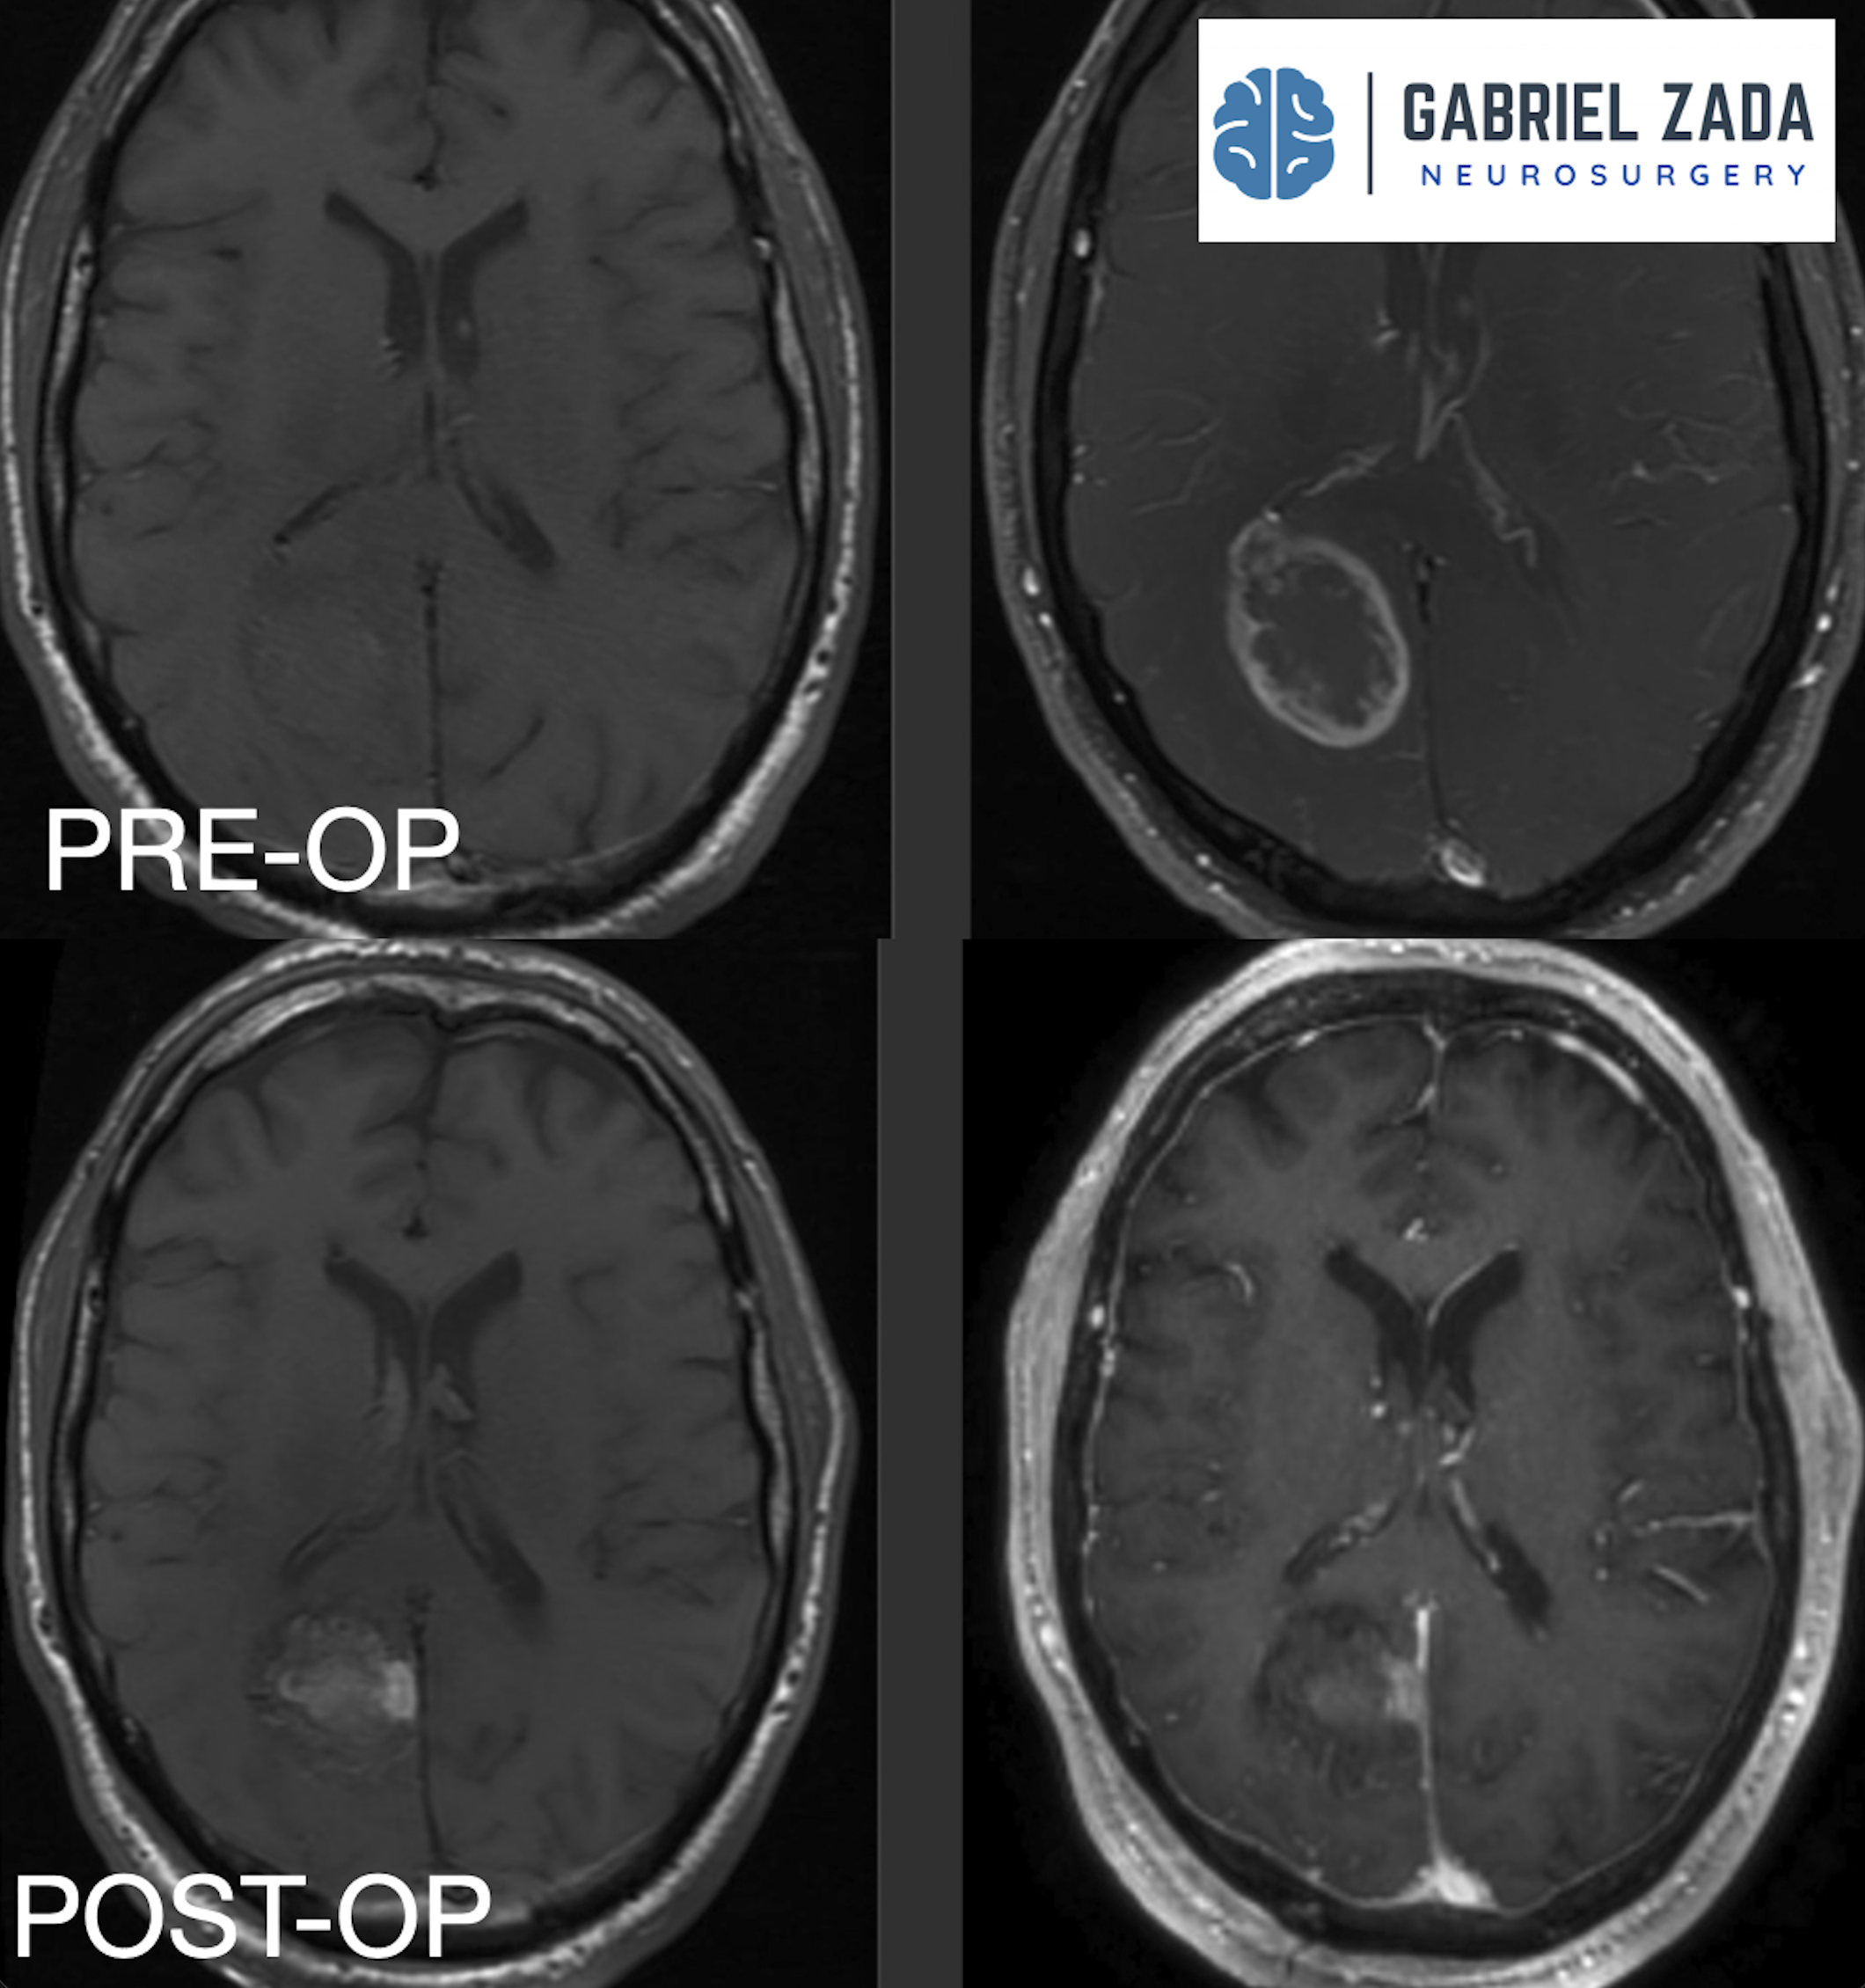

Explore this comprehensive gallery featuring pre‑ and post‑operative imaging of patients with skull‑base tumors treated by Gabriel Zada, MD, MS, FAANS, FACS. These cases highlight Dr. Zada’s expertise in advanced neurosurgical techniques and outcomes.

*Representative cases shown for educational purposes. All images de-identified. Individual results vary.